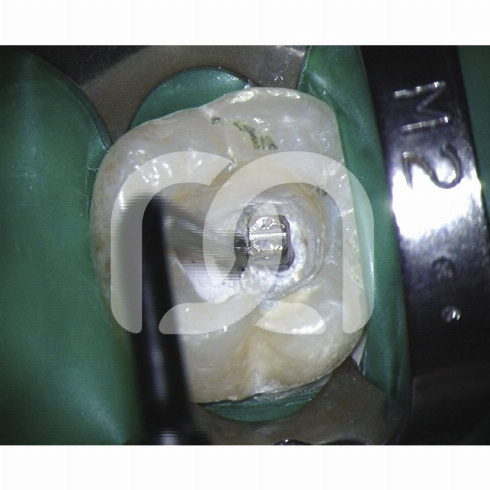

Insertsà ultrasons pour la finition de la cavité d'accès et la localisation des entrées canalaires.- Un insert endodontique Une indication clinique.- Start-X N° 1 : Finition des parois de la cavité d'accès.- Start-X N° 2 : Localisation du canal du 2ème canal racine mésio-vestibulaire.- Start-XN° 3 : Recherche et ouverture des canaux calcifiés.- Start-X N° 4 : Retrait des tenons métalliques.- Start-X N° 5 : Mise en forme de l'anatomie du plancher pulpaire. Caractéristiques - Partie active micro-fraisée : efficacité de coupe associée à une finition parfaite.- Port dirrigation : refroidit linsert et évite l'échauffement de la dent traitée, en particulier pour le descellement de tenon nécessitant une puissance élevée. Avantages - Une grande précision de travail.- Un gain de temps.- Excellente résistance à la fracture.